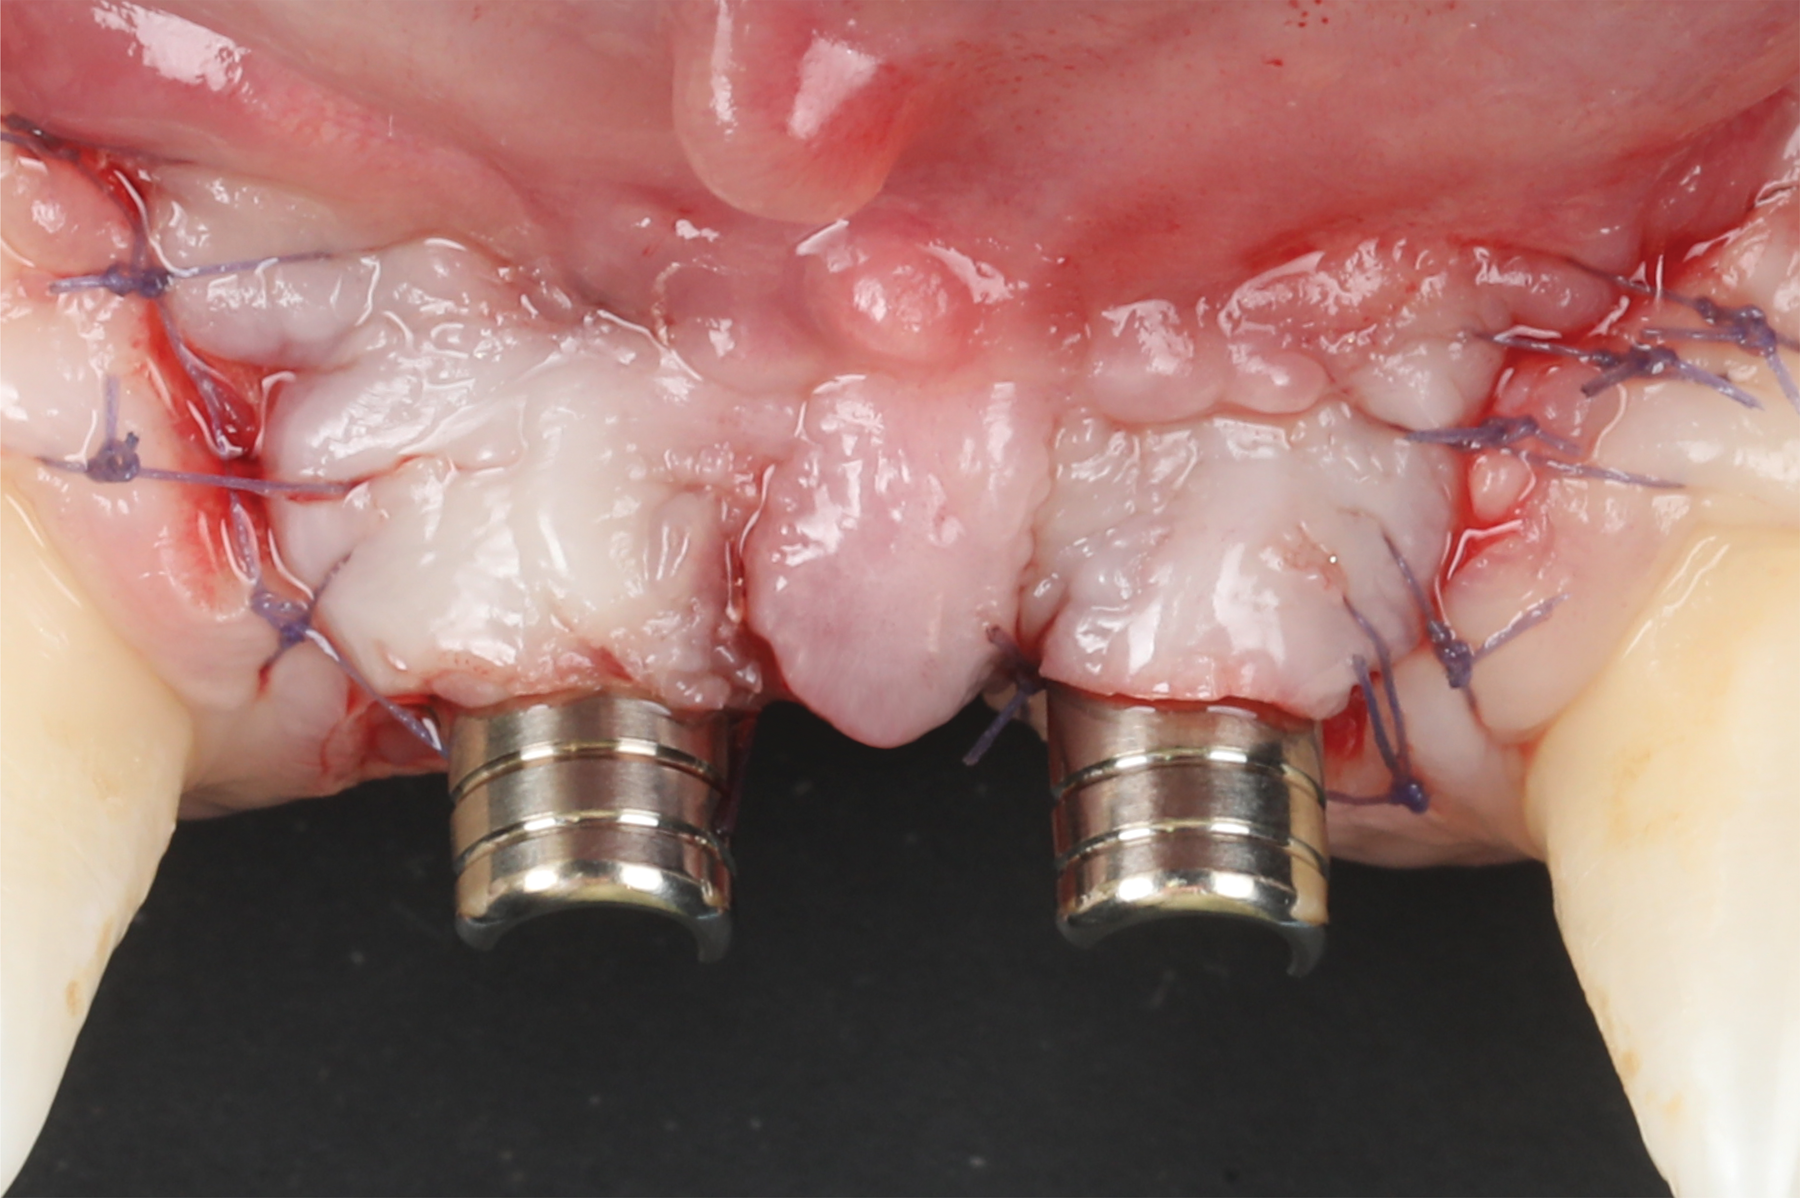

The flap was closed using simple interrupted sutures (7-0 PGA, butterfly), with the mid-portion of the flap folded and rolled to increase the thickness and height of the interproximal soft tissue between the two implants (Figure 12). 3D-printed temporary crowns were adapted to the flap and delivered (Figure 13). Further modifications of the temporary crowns were performed between 1 month and 3 months, when the final ceramic restorations were delivered.

Fig 12. Abutment connection and flap suturing.

Figure 12